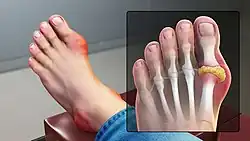

Gout presenting as slight redness in the metatarsal–phalangeal joint of the big toe

Gout of the left MP joint of the big toe -